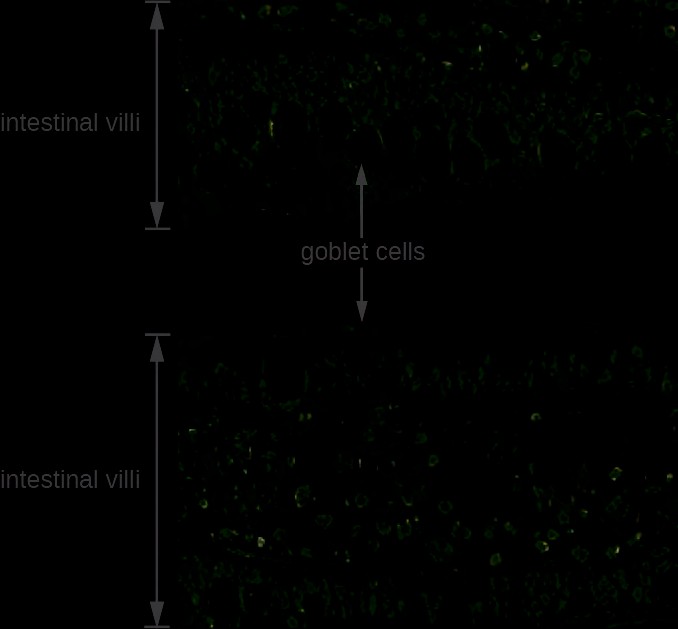

The GI tract has several other methods of reducing the risk of infection by pathogens. Small aggregates of underlying lymphoid tissue in the ileum, called Peyer’s patches (Figure 24.5), detect pathogens in the intestines via microfold

1. cells, which transfer antigens from the lumen of the intestine to the lymphocytes on Peyer’s patches to induce an immune response. The Peyer’s patches then secrete IgA and other pathogen-specific antibodies into the intestinal lumen to help keep intestinal microbes at safe levels. Goblet cells, which are modified simple columnar epithelial cells, also line the GI tract (Figure 24.6). Goblet cells secrete a gel-forming mucin, which is the major component of mucus. The production of a protective layer of mucus helps reduce the risk of pathogens reaching deeper tissues.

Figure 24.6 A magnified image of intestinal villi in the GI tract shows goblet cells. These cells are important in producing a protective layer of mucus.